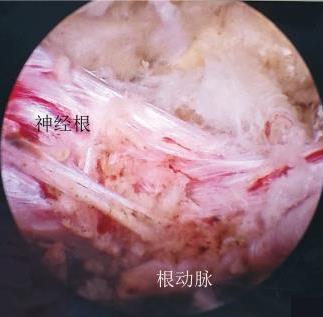

• 单通道非同轴脊柱内镜经椎间孔外入路(椎板外切迹)治疗极外侧椎间盘突出症的临床疗效观察

2026, 32(3):28-36. DOI: 10.12235/E20250050

摘要 (43) HTML (65) PDF 6.88 M (47) 评论 (0) 收藏

摘要:目的 观察单通道非同轴脊柱内镜经椎间孔外入路(椎板外切迹)治疗极外侧椎间盘突出症(FLLDH)的临床疗效。方法 回顾性分析2022年5月-2024年5月该院收治的,行单通道非同轴脊柱内镜经椎间孔外入路(椎板外切迹)治疗的FLLDH患者70例。于术前和术后,评估腰腿疼痛程度、腰椎功能和临床疗效。结果 相较于术前,术后3 d和3个月,患者下肢视觉模拟评分法(VAS)评分、腰部VAS评分、Oswestry功能障碍指数(ODI)、数字分级评分法(NRS)评分和Roland-Morris功能障碍问卷(RMDQ)评分明显降低,日本骨科协会(JOA)评分明显升高,差异均有统计学意义(P < 0.05);改良MacNab评分标准显示,末次随访时的优良率为94.28%。结论 单通道非同轴脊柱内镜经椎间孔外入路(椎板外切迹)治疗FLLDH,能明显改善患者腰腿疼痛和腰椎下肢功能,其具有创伤小、易操作、安全性高和疗效好等优点,值得在临床推广应用。